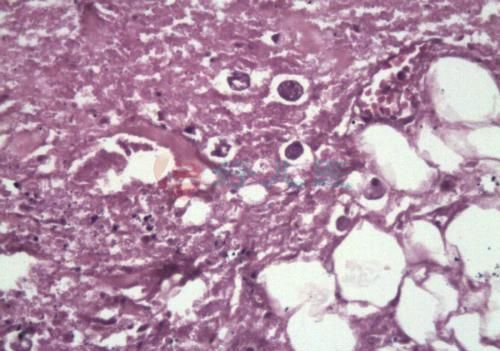

疫毒痢是因感受湿热疫毒,积滞肠腑,热毒炽盛而致突然发病,高热,昏迷,惊厥,便下脓血(或无)为主要表现的传染性疾病。西医学中的中毒性菌痢可参考本病辨证论治。

1、发病急暴,大便混有脓血,有腥臭味。或虽未见脓血便,而有高热、昏迷、惊厥,并可出现闭脱危象。

3、大便镜检可见大量红、白细胞(以白细胞为主),并有吞噬细胞。

4、取大便脓血部分(必要时肛门指检)培养,可有痢疾杆菌生长。